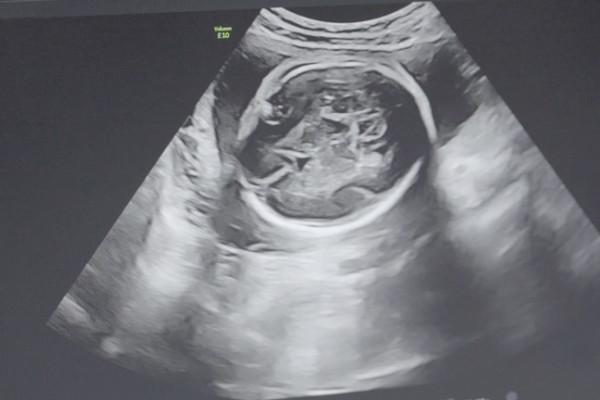

36歲女性服用克羅米芬後懷雙胞胎的減胎建議

克羅米芬是一種促排藥物,它能夠幫助女性卵巢內的卵子發育,並且是多個同時發育,所以說吃了這款藥物是可能會排出多個卵子,形成多胎妊娠的,如果是懷上的雙胞胎,需要根據女性的個人情況選擇要不要減胎,如果身體情況、骨盆條件等都比較合適的話,不用減胎,但如果身體存在疾病的話,就建議減胎了。藥品資訊商品名枸櫞酸氯米芬膠囊 成分氯米芬適用人群排卵障礙人群含量50mg價格30元 保質期60個月自然受孕出現雙胞胎的幾...